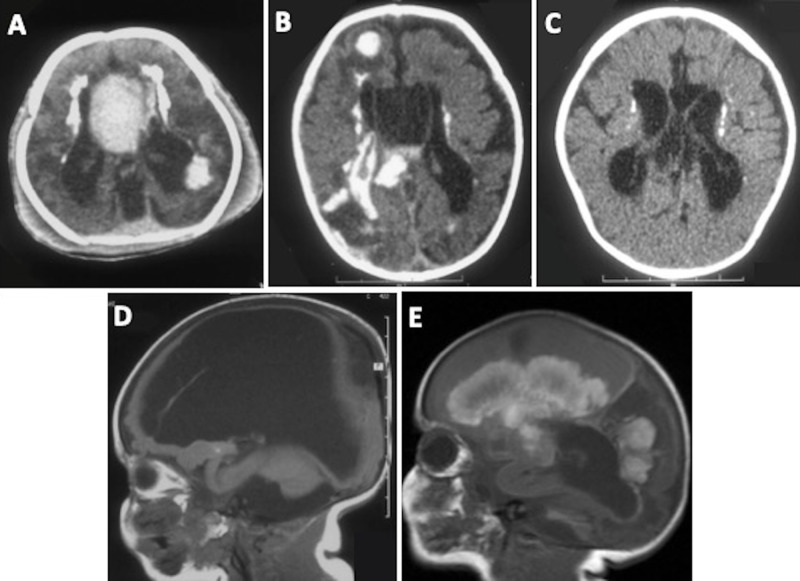

Hemorrhagic Destruction of the Brain, Subependymal Calcification, and Congenital Cataracts (HDBSCC) is a rare syndrome caused by biallelic mutations in the JAM3 gene with significant intrafamilial variability in clinical presentation and brain imaging phenotypes. The clinical presentation of HDBSCC includes severe recurrent hemorrhages involving the brain parenchyma and the ventricles beginning in utero and continuing in infancy together with dense central cataracts present at birth. This comprehensive review documents reported cases on this unique condition and describes its genetic, neuroradiologic and ophthalmic features. It should be included in the differential diagnosis of children with congenital cataracts and neurodevelopmental abnormalities. Unique clinical, imaging findings and genetic testing can help the diagnosis.

Abstract Image